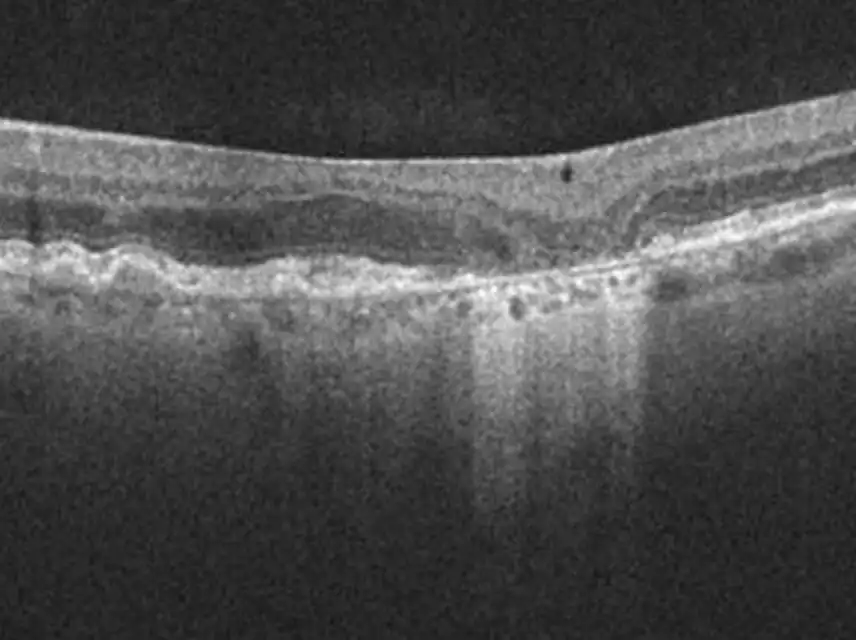

Optical Coherence Tomography (OCT)

Image courtesy of Dr. Mark Dunbar.

OCTEstablished as a key reference when assessing individuals for initial GA diagnosis9,10

Hypertransmission defects through the choroid point to areas of absent retinal pigment epithelium (RPE), photoreceptors (PR), and choriocapillaris layers.2